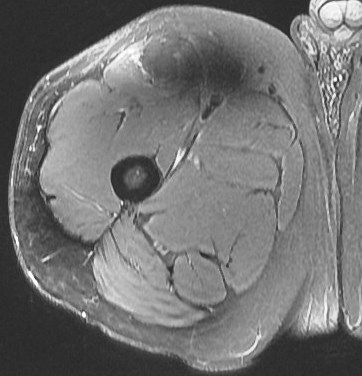

25 y/o work injury, soccer injury.

Maybe his soccer playing is his work? Who am I to ask questions. The indirect head goes on to form the central tendon. There is complete failure of the proximal myotendinous junction and there is an interposed acute hematoma. The hematoma is almost isointense to muscle. Reference article.

rectus femoris indirect head proximal myotendinous junction tear with hematoma( RID2698 )